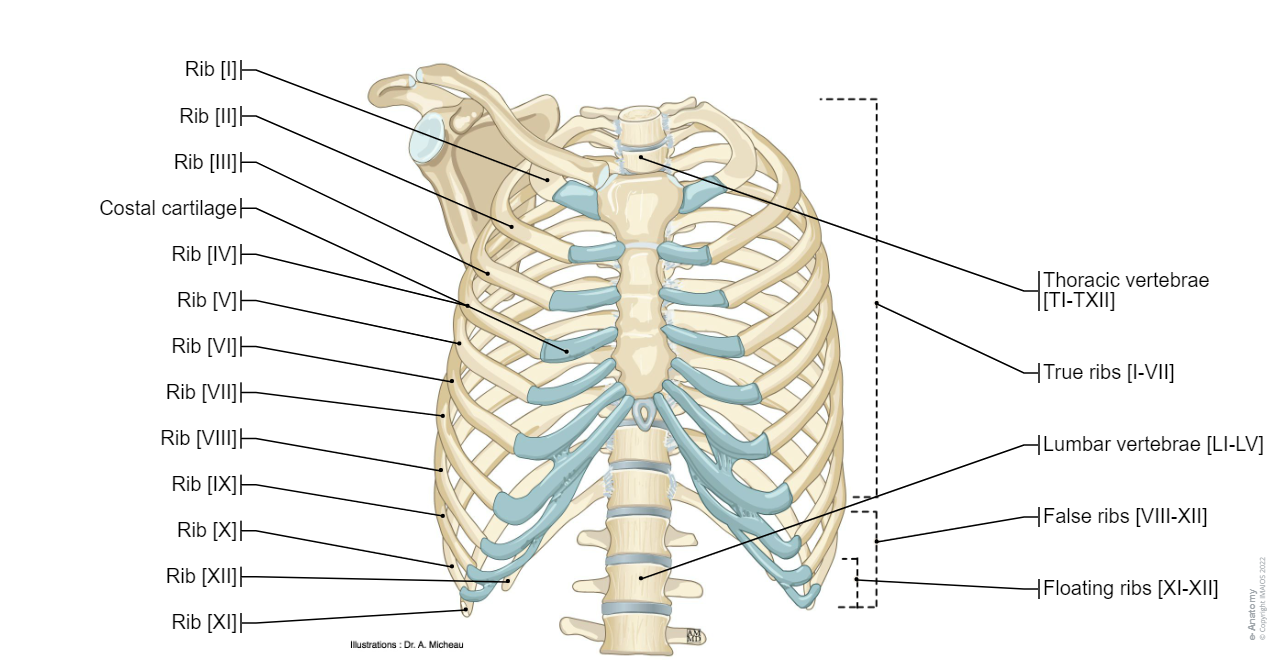

• Thoracic skeleton: patterns of bony anatomy of the thoracic cavity and rib cage in anterior and posterior view.

Anatomy of the thoracic wall and the breast (Illustrations) : Thoracic cage - Thoracic cavity

• Ribs: represents the anatomy of the ribs and muscle attachments